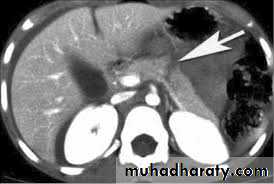

IV Contrast enhanced Computed Tomography Scan

contrast enhanced CT is indicated in the following situations:• if there is diagnostic uncertainty;

• in patients with severe acute pancreatitis, to distinguish interstitial from necrotising pancreatitis;

• in patients with organ failure, signs of sepsis or progressive clinical deterioration;

• when a localised complication is suspected, such as fluid collection, pseudocyst or a pseudoaneurysm.